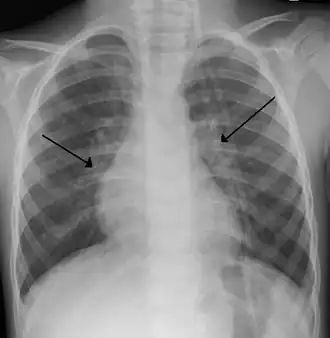

| Raio-x de criança com vírus sincicial respiratório | |

O diagnóstico é tipicamente feito por exame clínico. A radiografia de tórax é às vezes útil para excluir pneumonia bacteriana, mas não indicada em casos com sinais de complicações ou fatores de riscos como prematuridade. PCR para identificar o vírus também não é feito de rotina.[10]